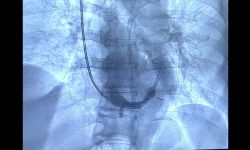

Eseguita per la prima volta all’Ospedale Di Venere una innovativa procedura interventistica per i pazienti affetti da cardiopatia ischemica cronica.

L’intervento, reso complesso da una importante deformazione della schiena, è stato eseguito dalla Unità di Cardiologia del San Giacomo di Monopoli. La donna sta bene ed è tornata a casa.